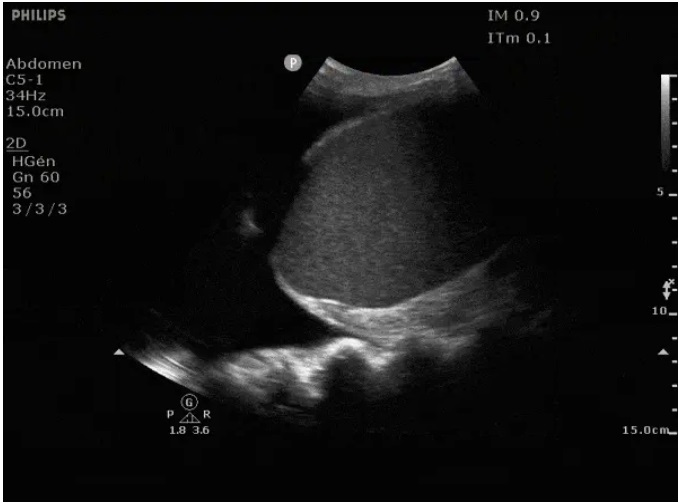

Aspect echographique d'une

pleuresie du sinus costo -diapragmatique postero-lateral

droit . La sinus costo-lateral droit remplir par

pleuresie hypoechogene |